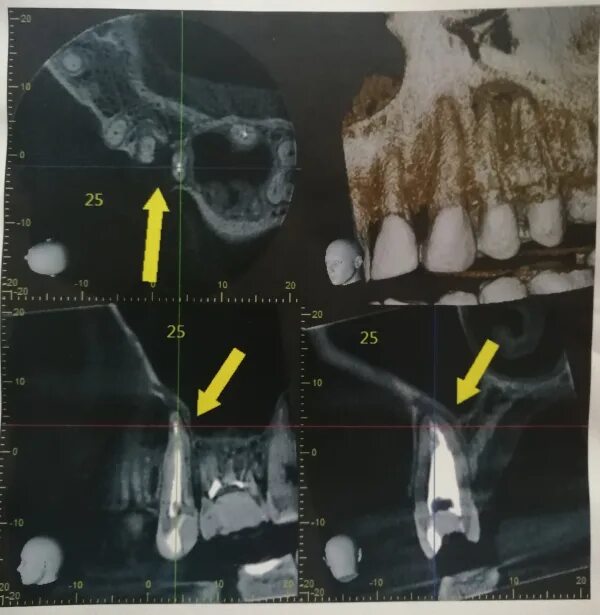

Киста зуба что это